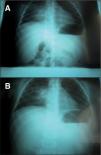

Niña de 3 años de edad que ingresa por presentar fiebre intermitente de mes y medio de evolución, prueba de tuberculina positiva de 20mm e imagen radiológica compatible con adenopatía hiliar y condensación del lóbulo superior derecho. Cuatro meses antes había sido ingresada por neumonía. Entre ambos procesos, la paciente había presentado un episodio de hemiparesia izquierda transitoria.

En el estudio realizado en el segundo ingreso se constata la similitud de las imágenes radiológicas torácicas entre la primera y la segunda estancia hospitalaria (fig. 1), lo cual, unido al episodio neurológico transitorio recogido en la anamnesis, hizo sospechar la posibilidad de que se tratara del mismo proceso infectivo tuberculoso y que el antecedente de hemiparesia se debiera a una participación cerebral del mismo. Por ello, se solicitó la realización de una resonancia magnética cerebral, en la que se puso de manifiesto la presencia de múltiples lesiones diseminadas de hiperseñal en secuencias T2 y FLAIR. Se observan captaciones nodulares intensas de gadolinio en la región hemibulbar derecha, hemipeduncular izquierda, temporal profunda medial izquierda, región occipital izquierda y región cortical parietal izquierda. Impresión diagnóstica: múltiples lesiones diseminadas de hiperseñal en la región infratentorial y supratentorial, lo cual parece sugerir la presencia de tuberculomas activos (fig. 2). Tras solicitar el consentimiento informado, se realizó punción lumbar, con los siguientes resultados: glucosa 47mg/dl, proteínas 27mg/dl, leucocitos 30/μl (polinucleares 10 % y mononucleares 90 %). Cultivo de bacilo de Koch en el líquido cefalorraquídeo negativo. En el estudio oftalmológico se encontró un pequeño foco en la retina bien delimitado compatible con tuberculoma coroideo. La serología VIH fue negativa.